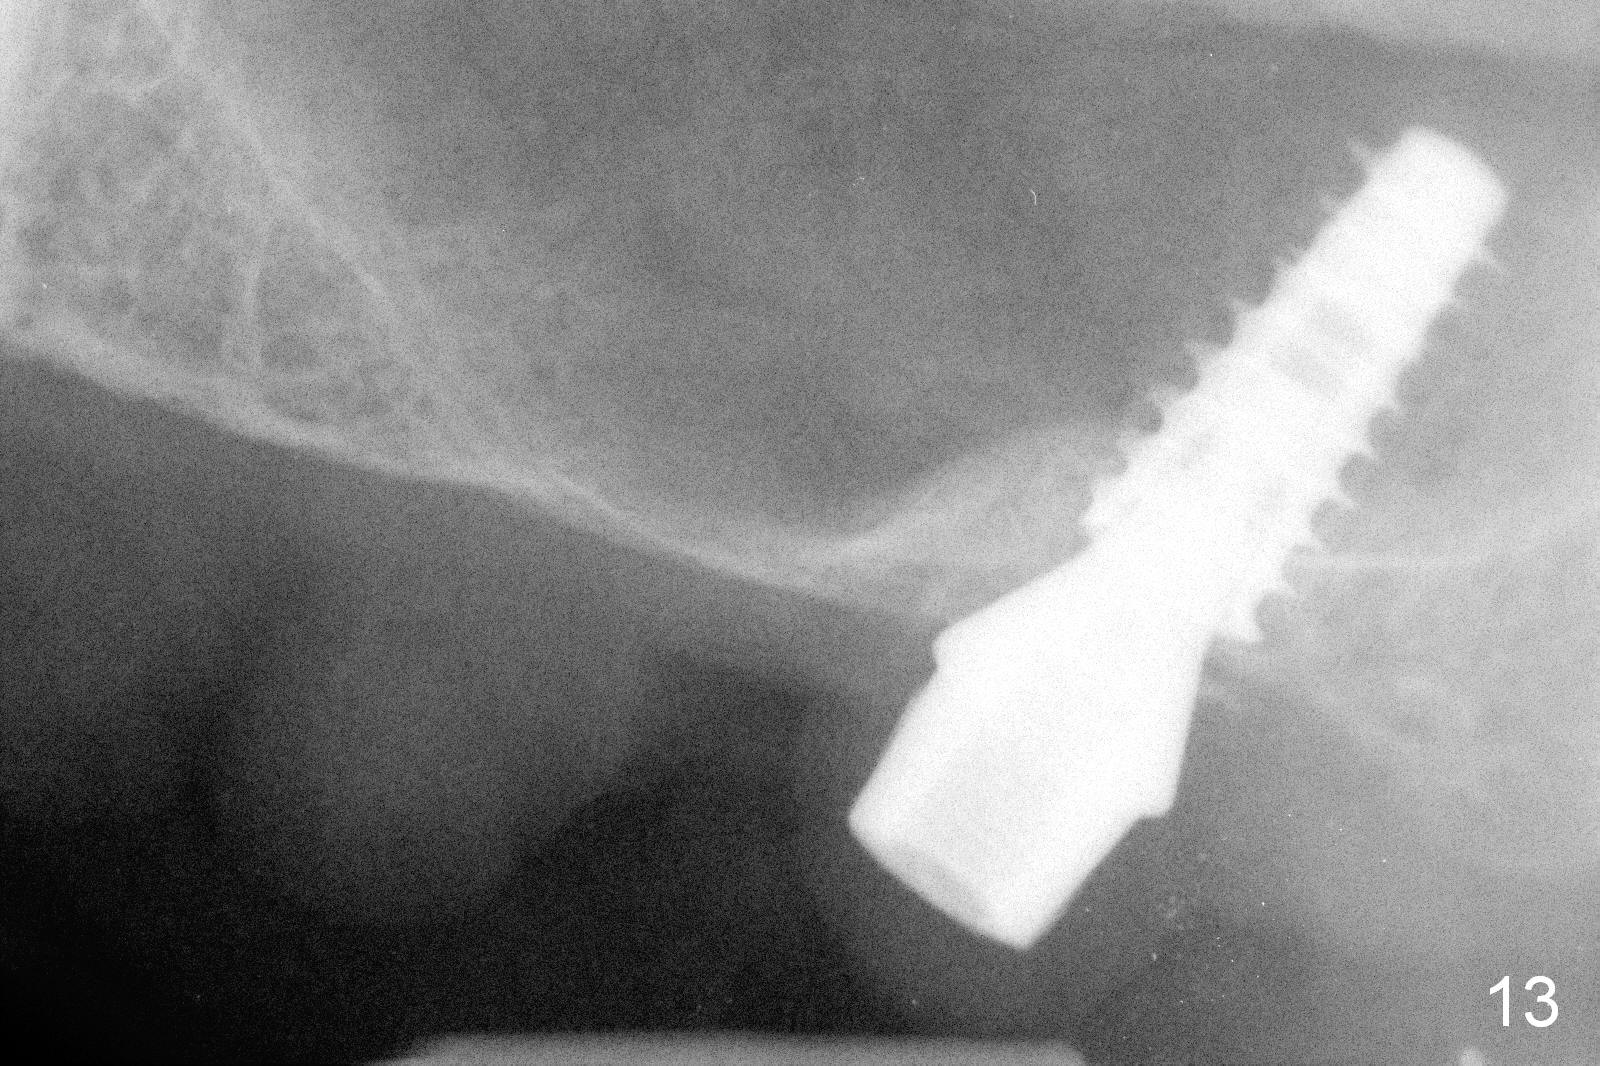

The bone density in the mesial socket appears to increase and becomes more homogenous 3 months postop (Fig.13). Impression is taken for final restoration.